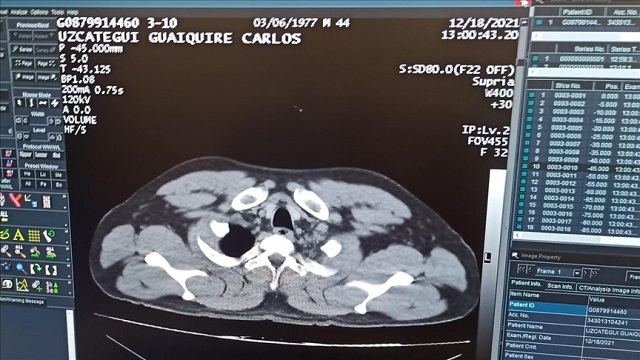

Tomografi kontrolünde de mide ve bağırsaklarda tespit edilen kapsüllerin ameliyatla alındığı şüpheli, taburcu olmasının ardından adliyeye sevk edildi.